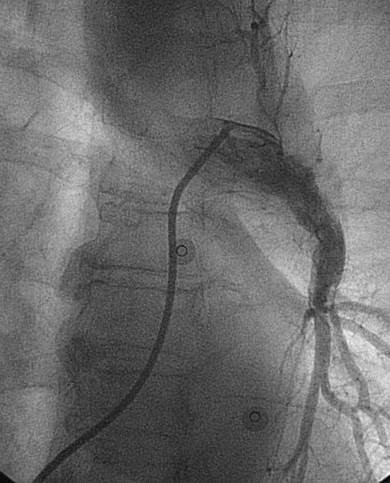

Paciente con hemorragia gastrointestinal activa que impide el uso de trombolíticos. Angiografía de la arteria pulmonar principal (más selectiva a la derecha) realizada con un catéter en espiral de 6 F en ángulo, que muestra la presencia de un trombo de gran tamaño dentro de las arterias pulmonares izquierda y derecha, y en las respectivas bifurcaciones lobares.

Se efectuó una trombectomía reolítica con el catéter PE de AngioJet® a través de una guía de angioplastia hidrófila de 0,035’’, partiendo de la arteria pulmonar izquierda y la bifurcación lobular inferior. La intervención se repitió en la arteria pulmonar derecha y en las bifurcaciones lobulares correspondientes. La intervención se detuvo debido a una bradiarritmia. Además, el tiempo de activación total se encontraba cerca del  límite recomendado (4 minutos).

A pesar del gran volumen de trombo eliminado, el angiograma final solo muestra una leve mejora de la obstrucción. Sin embargo, el objetivo del tratamiento es simplemente restaurar el flujo y no eliminar el trombo por completo, ya que incluso el modesto resultado de este angiograma estuvo acompañado de una considerable recuperación hemodinámica y de intercambio gaseoso.